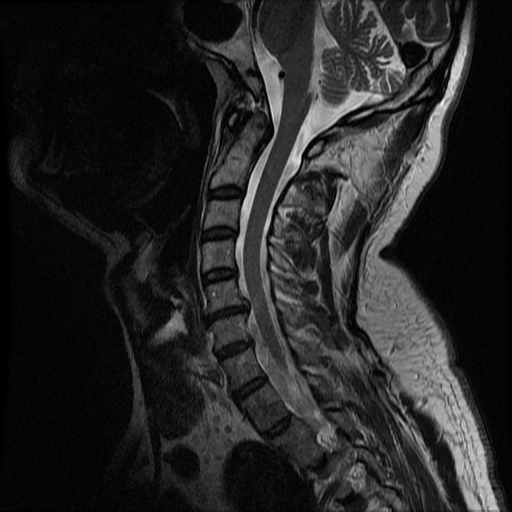

kręgosłupdyskopatiadyskopatia kręgosłupaoperacja kręgosłupaból